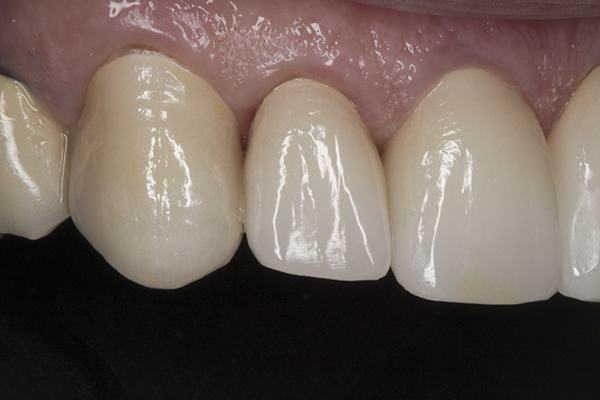

(38.) Postoperative right anterior, close-up view.

Figure 38

(39.) Postoperative anterior, close-up view.

Figure 39